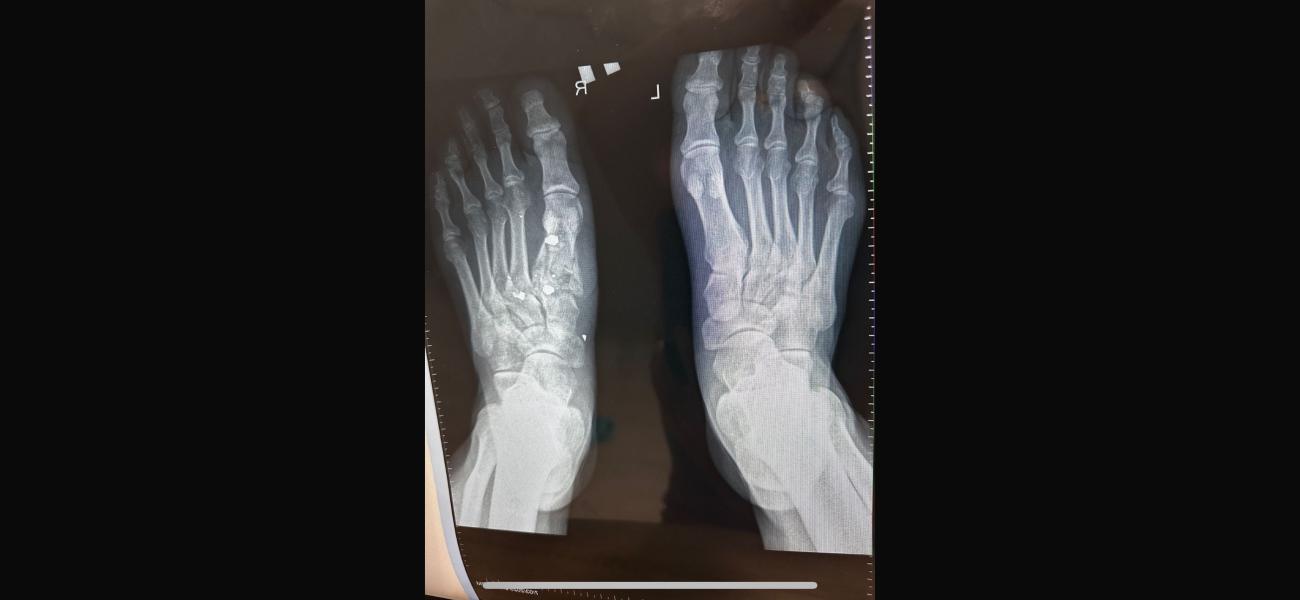

Ситуация следующая. Муж получил осколочное ранение, перелом плюсневой кости, осколок находиться в переломе прямо. Муж не чувствует 4х пальцев и не может шевелить ими. Хотя ранение было еще 22 января. К чему я, в госпитале усираются, что все само срастется и функционировать будет когда заживет, поэтому вынимать ничего не будут. Но как может срастись перелом, в котором осколок? В отпуске по ранению пытался лечь в госпиталь у нас в городе, до самого конца отпуска мурыжили что положат, ждите травматолога ( он бывает раз в сколько то дней, потому что по нескольким госпиталям бегает) когда мы наконец то 28го февраля попали к нему, он отказал в лечении. Сказал при части лечиться. Так вот хотелось бы услышать мнение врача. На случай если нам опять начнут говорить что все само пройдет.

П.с рентгены свои сделали, травматолога в частной не было в этот день, но сегодня сходим видимо просто в другую клинику, чтоб было на руках заключение. Но одно мнение специалиста хорошо, а два еще лучше

Что не шевелятся пальцы плохо, следите за сухожилиями

Если пальцы не шевелятся, возможно там ещё что-то мешает кроме осколка, может какое-то еще повреждение, проверьте по узи сухожилия